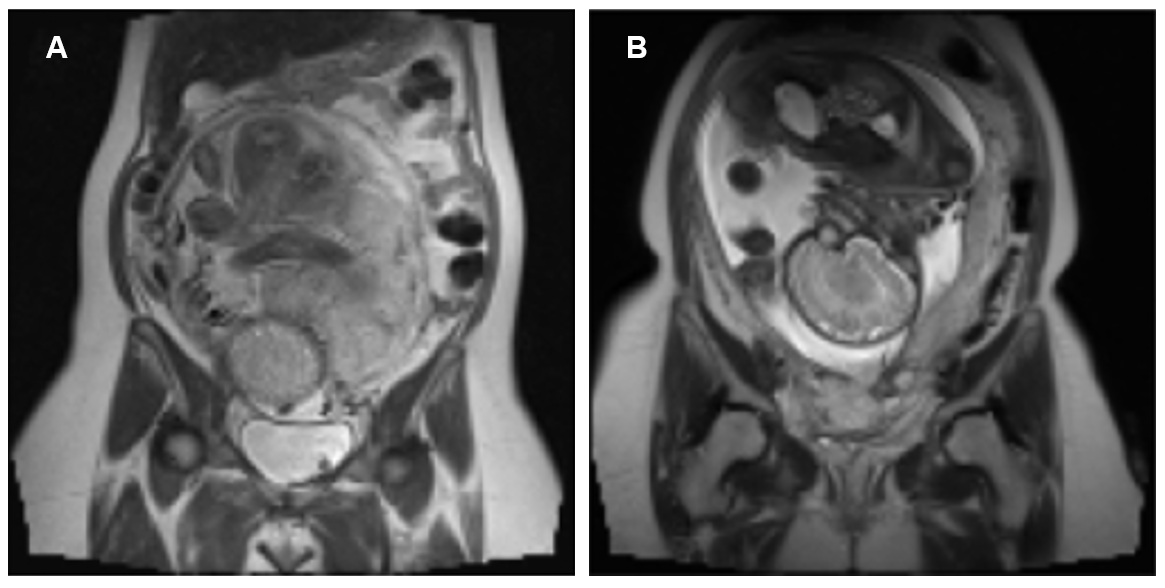

Current diagnostic practice combines clinical risk assessment with imaging, primarily ultrasound (US) and magnetic resonance imaging (MRI) [4]. Although, US imaging is commonly used for initial screening it has limitations in accurately assessing invasion depth and extent, especially with posterior placenta or bowel involvement. MRI offers complementary value through superior soft tissue contrast and larger field of view, providing detailed evaluation of invasion depth and adjacent organ involvement [2], [4]. Among different MRI sequences, T2-weighted imaging (T2WI) is most common for placental assessment and T1-weighted imaging (T1WI) reflect bleeding conditions [5]. Key MRI signs of PAS include T2-dark intraplacental bands, focal interruption of myometrial border, abnormal vascularity (Fig. 1) [6, 7]. However, the interpretation of these complex imaging features remain qualitative, requires significant radiological expertise, and prone to inter-observer variability [8], presenting the need for objective diagnostic methods.

Refer to caption

Figure 1: MRI signs of PAS: (A) Intraplacental bands, (B) Myometrial border interruption, and (C) Abnormal vascularity. [7]